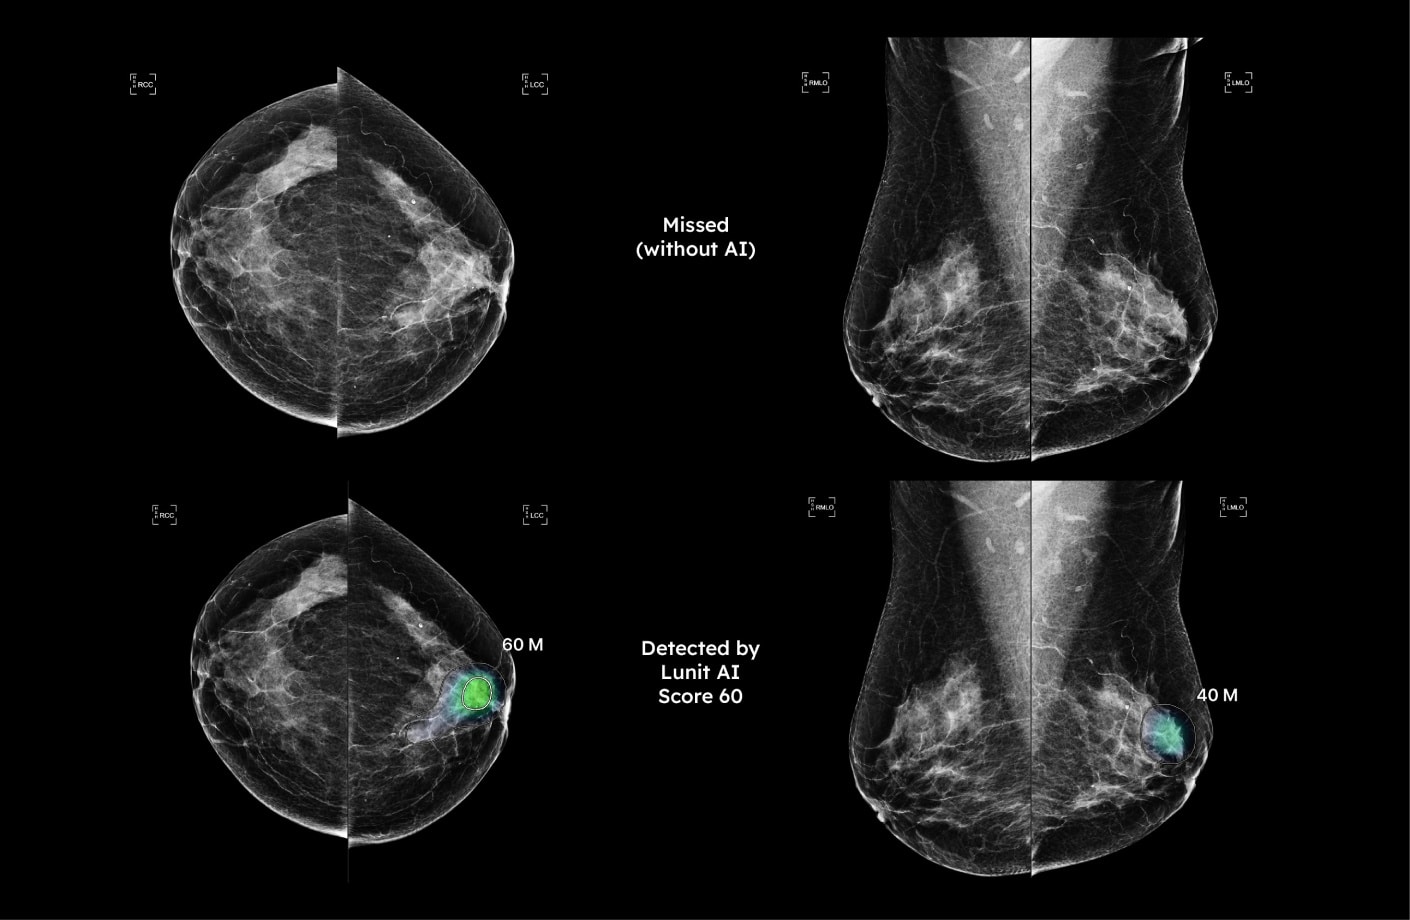

Comparison of mammograms showing lesion missed by radiologist but detected by AI mammography software, leading to earlier cancer diagnosis.

A second digital analysis

Lunit INSIGHT is an AI-powered software that analyzes mammogram images and alerts the radiologist of suspicious areas. Serving as a valuable second opinion, Lunit INSIGHT provides another layer of scrutiny and detects abnormalities that might not be visible to the human eye.